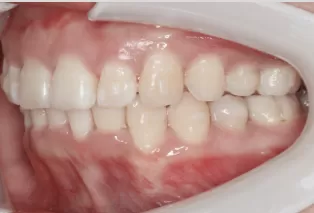

Femme, 25 ans. Plainte principale: dents saillantes et mal alignées, nécessitant un traitement orthodontique.

Ajustez les relations molaires gauche et droite par la distalisation simultanée des molaires supérieures et inférieures. Aligner la dentition en rétractant les dents antérieures. Avancez la mandibule pour améliorer le profil et le sourire gommeux.

Avant le traitement

Photos intra-orales